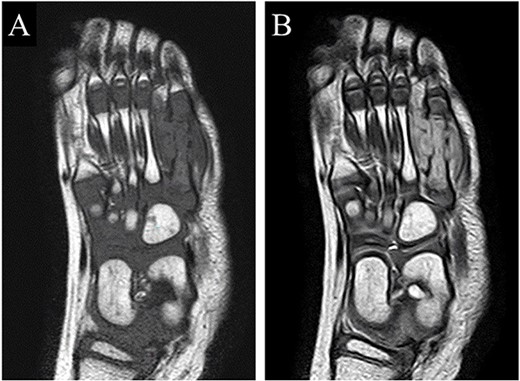

A 21-month-old Japanese female infant presented with a swollen mass on the dorsolateral aspect of the left foot. Her parents noticed the mass and brought the patient to our hospital. The patient had no past medical histories or complications prior to the occurrence. In addition, she received the BCG vaccine at the age of 4 months in Japan. At first visit to our hospital, physical examination revealed the ~3 × 3 cm mass was located on the dorsolateral aspect of the left foot and was hard accompanied by local heat (Fig. 1). Plain radiographs of the left foot showed a lytic lesion without periosteal reaction in the fifth metatarsal bone (Fig. 2). Magnetic resonance imaging (MRI) showed an isointense lesion on T1-weighted images and a hyperintense lesion on T2-weighted images around and within fifth metatarsal (Fig. 3). Gallium scintigraphy revealed intense uptake in the patient’s left foot (Fig. 4). In addition, laboratory examination was within normal. Based on medical history, clinical and imaging findings, we considered the possibility of neoplasia or osteomyelitis and performed an open debridement and biopsy of the lesion to make a diagnosis. The lesion was yellow and consisted of weak, adipose-like tissue that surrounded and continued into the inferior of the fifth metatarsal bone (Fig. 5). The lesion inside and outside the bone was resected as much as possible. Histopathologic examination of the lesion showed granulomatous inflammation including anaplastic giant cells, Langerhans-type giant cells and caseous necrosis (Fig. 6). Based on these results, TB or BCG osteomyelitis was considered as a diagnosis. The tuberculin test was positive, but the QuantiFERON TB test was negative. In addition, samples analyzed using polymerase chain reaction did not identify M. tuberculosis, but did identify the BCG Tokyo-172 strain. Per these findings, the patient was diagnosed with BCG osteomyelitis of the fifth metatarsal and oral treatment with anti-TB medicine including isoniazid (100 mg/day) and rifampicin (150 mg/day) was started. Clinical findings included reduction in swelling of the mass and gradual remodeling of the lytic lesion of the fifth metatarsal on plain radiographs (Fig. 7). However, 10 months after starting the anti-TB treatment, the mass recurred, and MRI revealed a residual high-intensity lesion around and inside the fifth metatarsal on T2-weighted fat-suppressed images (Fig. 8). It was determined that the lesion was difficult to control with anti-TB treatment alone, so an open debridement for the lesion was performed again. Histopathologic examination of the lesion revealed an epithelioid granuloma with necrosis. Therefore, the anti-TB treatment was continued. Six months after the second surgery, clinical and radiographic image findings showed complete improvement (Fig. 9). As a result, anti-TB treatment was ended. At the time of writing this report, 8 years after starting anti-TB treatment, there has been no recurrence.

MRI revealed that a high-intensity lesion remained around and inside the fifth metatarsal on T2-weighted fat-suppressed images.